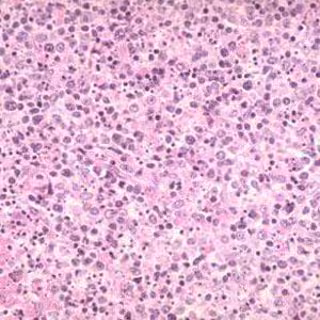

El trabajo demuestra el desarrollo de células madre pluripotentes inducidas (células iPS) a partir de fibroblastos humanos y de ratón utilizando una secuencia de ADN llamada 'piggyBac' que puede moverse alrededor de la célula. Al combinar este método con un único vector se administram todos los factores en un único lugar del cromosoma y después se provoca su activación.

Las células iPS tienen un gran potencial en aplicaciones desde la medicina regenerativa a las pruebas toxicológicas y el análisis de fármacos pero los métodos actuales suponen la administración de virus a los genes que podrían causar anomalías en las células inducidas.